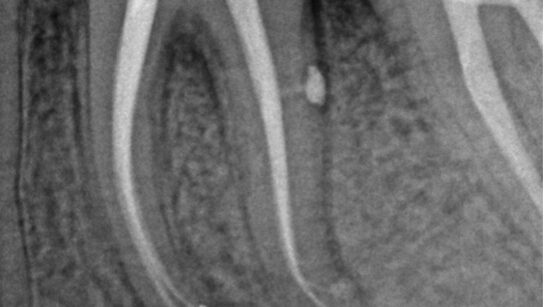

Los casos de retratamiento a menudo se complican y es por eso por lo que el retratamiento requiere…